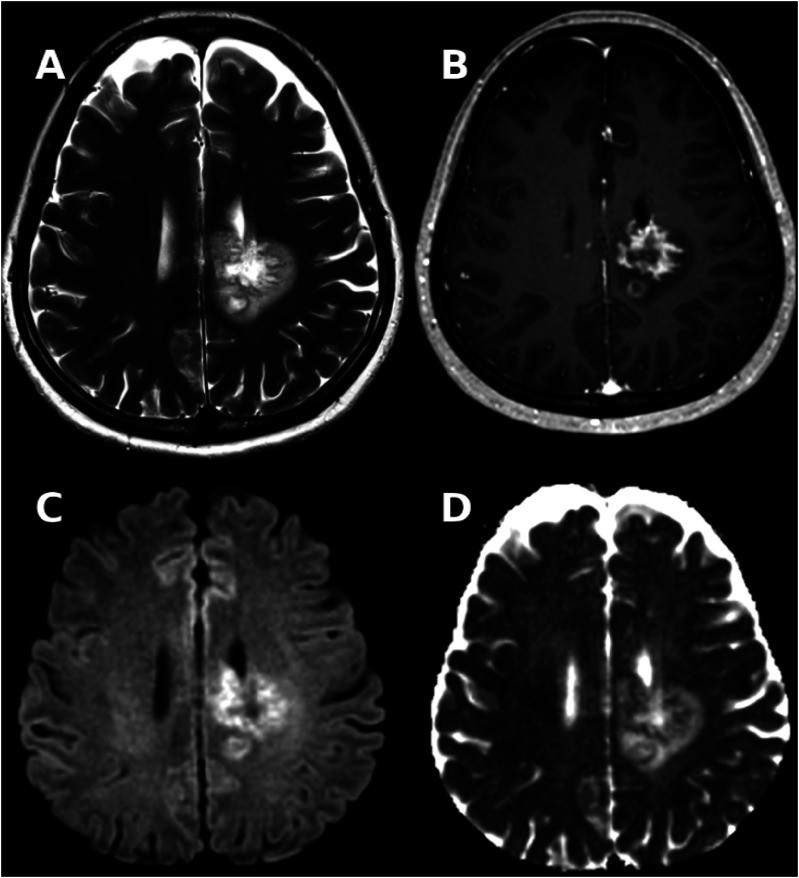

我们报告了一例55岁女性伴甲状腺间变性癌(ATC)的副肿瘤性肿瘤性脱髓鞘,同时回顾了所有与非中枢神经系统肿瘤相关的肿瘤性脱髓鞘病例。在本病例中,患者出现了右侧亚急性感觉运动偏瘫。最初的脑部MRI显示双侧额顶叶膨大性肿块病变,有明显的钆摄取和肿块效应。脑脊液显示csf特异性III型寡克隆带,细胞计数、蛋白和病原体检测均为阴性。脑组织活检显示脱髓鞘、t细胞浸润和泡沫状巨噬细胞。全身CT示甲状腺间变性癌。尽管接受了类固醇、血浆置换、利妥昔单抗和癌症治疗,患者还是因临床波动和癌症进展而死亡。除了我们的病例外,在新诊断的颅外肿瘤患者中报道了9例肿瘤性脱髓鞘,最常见的是精原细胞瘤生殖细胞肿瘤(7/10)。8/10(80%)患者为男性,平均诊断年龄为52.9岁,95% C.I.[43.8, 62.0]。5/10患者表现为感觉运动偏瘫和/或精神错乱/神经认知障碍。4/10有视力缺陷,2/10有失语。所有病例均同时或在神经系统表现后诊断出肿瘤。所有病例最初表现为孤立病变。恶性肿瘤特异性治疗和类固醇治疗在不同的团应用。此外,2/10的患者进行了血浆置换,1/10的患者接受了静脉注射免疫球蛋白。在大多数病例中,包括本病例,部分神经系统改善被记录,而恶性肿瘤通常进展。据我们所知,这是首次报道与ATC相关的副肿瘤肿瘤性脱髓鞘,强调了对这些患者进行彻底检查的重要性。这是首次报道的与ATC相关的副肿瘤肿瘤性脱髓鞘,强调了在类似患者中采用综合诊断方法的必要性。

We present a case of paraneoplastic tumefactive demyelination in a 55-year-old female with an underlying anaplastic thyroid carcinoma (ATC), alongside a review of the literature on all cases of tumefactive demyelination associated with non-CNS neoplasia. In the presented case the patient developed a right-sided subacute sensorimotor hemiparesis. The initial cerebral MRI revealed a bilateral frontoparietal tumefactive mass lesion with marked gadolinium uptake and mass effect. Cerebrospinal fluid revealed CSF-specific oligoclonal bands type III, with negative cell count, protein and pathogen testing. Brain biopsy indicated demyelination and T-cell infiltrates and foamy macrophages. A body CT revealed an anaplastic thyroid carcinoma. Despite steroids, plasma exchange, rituximab, and cancer treatment, the patient died due to clinical fluctuation and cancer progression. In addition to our case 9 cases of tumefactive demyelinating have been reported in patients with newly diagnosed extracranial neoplasia, most commonly seminoma germ cell tumour (7/10). 8/10 (80%) of patients were male, with mean age at diagnosis was 52.9 years 95% C.I. [43.8, 62.0]. 5/10 patients presented with sensorimotor hemiparesis and/or confusion/neurocognitive deficits. 4/10 with visual deficits and 2/10 with aphasia. In all cases neoplasia was diagnosed simultaneously or after neurological manifestations. All cases presented initially as solitary lesions. A malignancy specific-treatment as well as steroid treatment in different regiments were applied. In addition in 2/10 plasmapheresis was implemented and 1/10 patients received intravenous immunoglobulins. In the majority of cases including the presented case partial neurological improvement was documented whereas malignancy usually progressed. To our knowledge, this is the first report of paraneoplastic tumefactive demyelination associated with an ATC highlighting the importance of a thorough workup in these patients. This is the first reported case of paraneoplastic tumefactive demyelination associated with ATC, underscoring the necessity of a comprehensive diagnostic approach in similar patients.